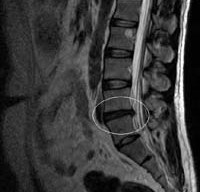

Эффективность мануальной терапии при наличии у пациента данного диагноза доказана на практике, именно поэтому методика активно используется и в традиционной медицине. Однако лечение может быть начато после точного определения местоположения грыжи. Для этого пациенту может быть назначена магнитно-резонансная томография, поскольку на рентгенографии не всегда можно выявить патологию.